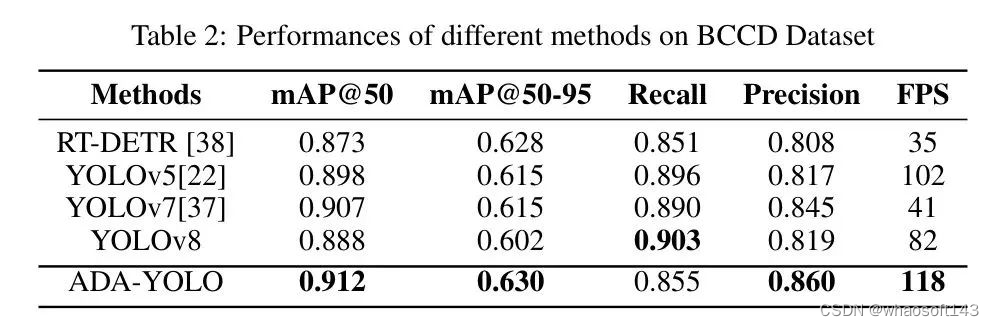

2.0 ADA-YOLO

一种内存高效的 ADA-YOLO 模型,该模型利用新颖的架构和训练策略来增强医学图像中多目标检测的鲁棒性。通过在各种数据集上的实验,证明了 ADA-YOLO 在处理医学图像中的遮挡相关挑战方面具有优越性能。模型在准确局部化和分类多个目标方面,即使在遮挡条件下也表现出卓越性能。YOLOv8+注意力+Adaptive Head,相对YOLOv8,mAP提升3%+118FPS

作者在BCCD(血液细胞计数和检测)数据集上进行了实证实验,以评估ADA-YOLO的有效性。结果表明,在BCCD数据集上,与YOLOv8相比,ADA-YOLO在mAP(平均平均精确率)方面取得了更好的性能,而所需的资源比YOLOv8少3倍以上。这表明作者提出的这种方法是有效的。

Results

实验结果如下:与 Faster R-CNN(快速 R-CNN)、SSD(快速 SSD)、YOLOv5(YOLO v5)、YOLOv7(YOLO v7)和 YOLOv8(YOLO v8)等基准相比,提出的 ADA-YOLO 方法。

RT-DETR(实时检测 Transformer)是一种基于 Transformer 架构和端到端学习的新颖目标检测方法,与基于区域 Proposal 的传统目标检测方法(如 Faster R-cnn)不同。RT-DETR 试图通过完全消除手动设计组件(如 Anchor 框和非极大值抑制)来使目标检测的训练和推理更加简单和高效。RT-DETR 使用自注意力机制全局编码一组特征向量,并引入一个特殊的"类别嵌入"向量来表示没有目标的地点。

ADA-YOLO 模型针对医学影像中的多目标检测,解决了物体遮挡或截断等在医学影像中常见的挑战性问题。如图 4 所示,提出的检测方法可以成功检测到任何大小的红细胞缺失,与基准相比是一个很大的改进。ADA-YOLO 在所有类别中具有 0.918 的召回率,优于基准。

与此同时,除了卓越的定量性能外,ADA-YOLO 在内存使用方面也非常高效。为了证明这一点,主要实验已经进行,并显示 YOLOv8 模型预测所有样本需要 26.9 MB 的内存和 35.1 GFLOPs 的计算能力,而作者的方法只需要 8.7MB 的内存,比 YOLOv8 节省了 3 倍的内存,并仅计算了 9.4 GFLOPs。